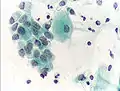

Micrograph of a normal pap smear Micrograph of a Pap test showing a low-grade intraepithelial lesion (LSIL) and benign endocervical mucosa. Pap stain.

Micrograph of a Pap test showing a low-grade intraepithelial lesion (LSIL) and benign endocervical mucosa. Pap stain. Micrograph of a Pap test showing trichomoniasis. Trichomonas organism seen in the upper right. Pap stain.